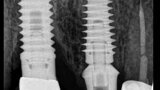

Fig. 18: A periapical radiograph

with a drill in place confirmed that the apex length had been reached and that all the gutta-percha had been removed.